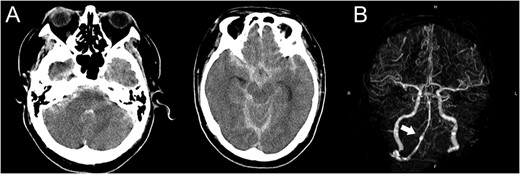

A 48-year-old man was admitted to our hospital because of loss of consciousness after a sudden nuchal pain. Brain computed tomography (CT) showed diffuse SAH (Fig. 1A). The following CT angiogram showed a fusiform aneurysm at the right vertebral artery with contralateral hypoplasia (Fig. 1B). The endovascular procedure was performed under general anesthesia. The patient received a loading dose of 200 mg of aspirin and 300 mg of clopidogrel via a nasogastric tube. A preoperative angiogram showed VAD with a blister at the pseudolumen (Fig. 2A). Initially, a stent (Enterprise, 4.5 mm × 37 mm; Codman, Raynham, MA, USA) was deployed from the basilar artery to the right vertebral artery. A second stent (Enterprise2, 4.0 mm × 30 mm) then overlapped the first stent, covering the pseudolumen (Fig. 2B). Coiling was performed from a microcatheter (Excelsior SL-10/45; Boston Scientific, Fremont, CA, USA), which was jailed in the pseudolumen. After the first coil perforated the blister, a balloon catheter (Scepter C, 4.0 mm × 15 mm; Microvention, Tustin, CA, USA), which was exchanged with a stent delivery catheter, was inflated in the stent. All five small platinum coils (Target nano, 2 mm × 4 cm and 1.5 mm × 2 cm; Stryker, Fremont, CA, USA) completely occluded the pseudolumen (Fig. 2C), and the right vertebral artery was preserved (Fig. 2D). Magnetic resonance imaging, which was obtained 3 weeks after the procedure, showed right cerebellar infarction without damage of the brainstem (Fig. 3). The patient recovered and returned to his former job after 2 weeks of intensive care and 3 months of rehabilitation therapy. An angiogram, which was obtained 6 months after procedure, showed no recurrence of VAD (Fig. 4).

(A) Preoperative angiogram shows a dissecting aneurysm with a blister. (B) The first stent was deployed across the aneurysm and the second stent overlapped the first stent. (C) Coiling was performed under the support of a balloon catheter after the first coil perforated the blister. (D) Complete obliteration of the pseudolumen was achieved and the parent artery was preserved.